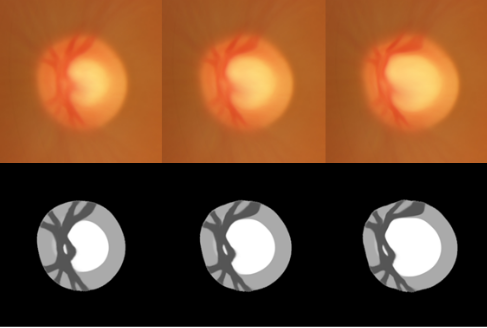

- Atlas-Based Score for Automatic Glaucoma Risk Stratification

- Computerized Medical Imaging and Graphics, 2020

- Proliferative Diabetic Retinopathy Characterization Based on the Spatial Organization of Vascular Junctions in Fundus Images

- IEEE Intl. Symp. on Biomedical Imaging (ISBI), 2017

- A Multi-Scale Tensor Voting Approach for Small Retinal Vessel Segmentation in High Resolution Fundus Images

- Computerized Medical Imaging and Graphics, 2016

- Red Lesion Detection using Dynamic Shape Features for Diabetic Retinopathy Screening

- IEEE Trans. Medical Imaging, vol. 35 (4), 2016

- Automatic Detection of Microaneurysms and Haemorrhages in Fundus Images using Dynamic Shape Features

- IEEE Intl. Symp. on Biomedical Imaging (ISBI), 2014

- Automatic Multiresolution Age-related Macular Degeneration Detection from Fundus Images

- SPIE Medical Imaging, Computer-Aided Diagnosis, 2014

- Glaucoma Detection based on Local Binary Patterns in Fundus Photographs

- SPIE Medical Imaging, Computer-Aided Diagnosis, 2014

- 2016-2017: a project on Automatic classification of fundus images, a Collaborative Research and Development grant from the Natural Sciences and Engineering Research Council of Canada (NSERC), in collaboration with DIAGNOS

- 2013-2016: a project on Real-time Analysis of Fundus Images, a Collaborative Research and Development grant from the Natural Sciences and Engineering Research Council of Canada (NSERC), in collaboration with DIAGNOS